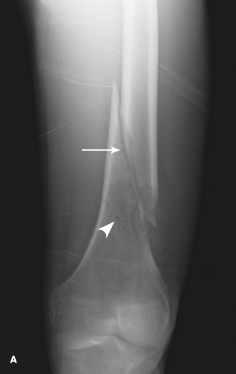

Wael AlJaroudi, MD, MS

<div class="column"><p>A 41-year-old woman presented to the emergency department (ED) with a 3-day history of left thigh pain and swelling. She denied any precipitating trau-...